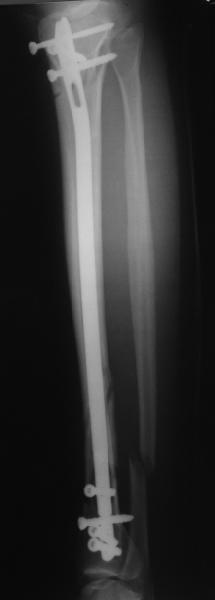

Re: Проксимальный и дистальный переломы tibia

Сделали все-таки стержнем. На всякий случай просверлил дополнительное проксимальное отверстие, так что получилось три 45-градусных винта.

В дистракторе провеи спиц поболше в прокисмальном отделе, чтобы не разобщить фрагменты при сгибании колена. Комментарии и критика приветствуются.

We proceeded with nailing using a small wire distractor, with few wires at the proximal end to prevent displacement with forced knee flexion. Images attached. Comments and critics are welcome.